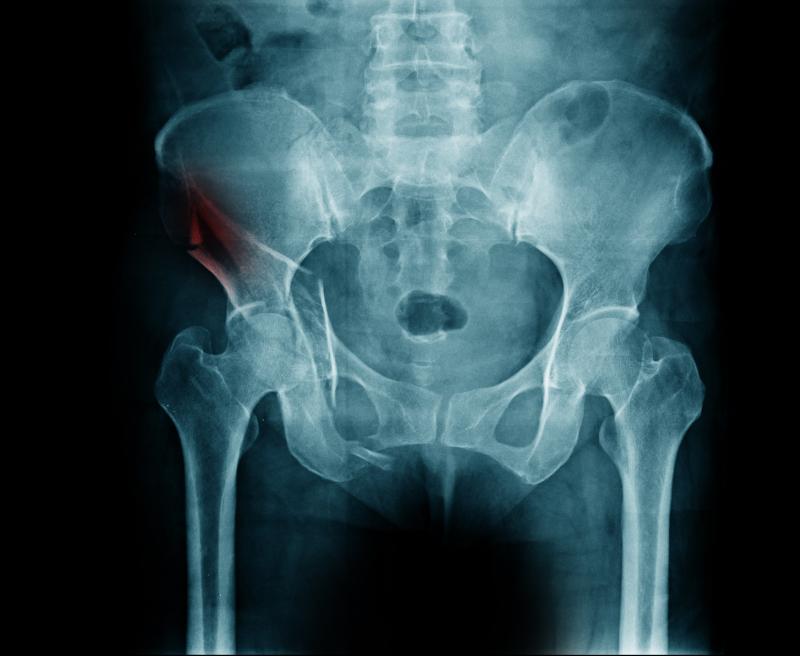

Bisphosphonate users vs nonusers had fewer arm (20.7 percent vs 26.4 percent; p<0.0001) and femur (28.9 percent vs 31.2 percent; p=0.005) fractures but more spinal (25.8 percent vs 19.0 percent), rib (40.0 percent vs. 32.2 percent), and skull (10.1 percent vs 8.7 percent) fractures.